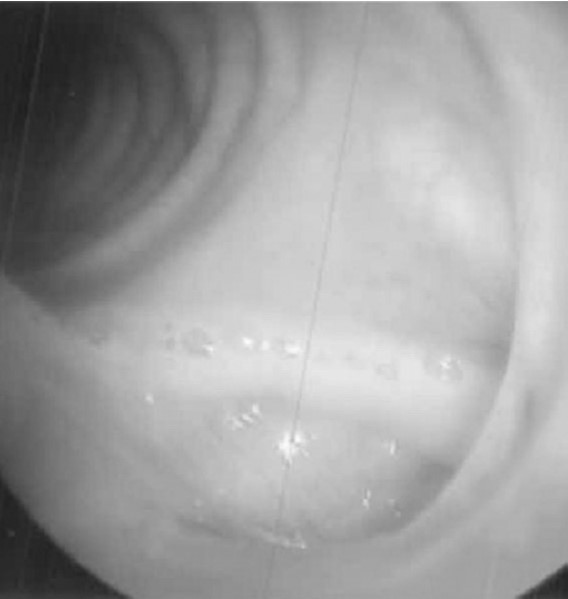

Fig. 4.

Bronchoscopic view revealed the pus flows into normal bronchus through bronchopleural fistula